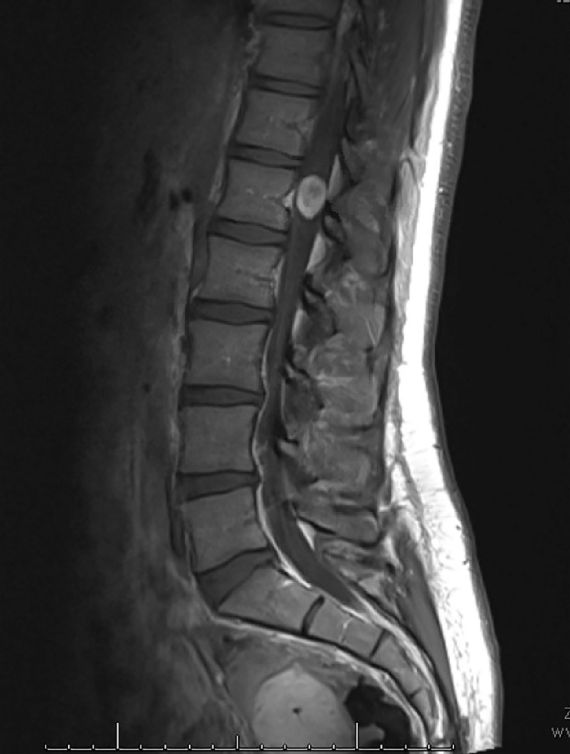

Στις 17 Ιανουαρίου το 2020, λίγες εβδομάδες μετά τη μαγνητική τομογραφία που είχε υποβληθεί, για να δει τι ήταν αυτοί οι ξαφνικοί πόνοι που την έπιασαν στην πλάτη, η ΝτεΣιλντς υποβλήθηκε σε χειρουργική επέμβαση στο Σικάγο, για να αφαιρέσει τον όγκο που είχε στο μέγεθος του σταφυλιού, στον νωτιαίο μυελό της. Η διαδικασία που αναμενόταν να είναι μια τρίωρη χειρουργική επέμβαση για την αφαίρεση του οσφυϊκού νωτιαίου σβαννώματος εξελίχθηκε σε μια διαδικασία… εννέα ωρών.

Ο καλοήθης όγκος της ΝτεΣιλντς, είχε διάμετρο 2-2½ εκατοστά και συμπίεζε τον νωτιαίο μυελό της: «Σκεφτείτε το, σαν ένα σταφύλι που πιέζει αυτό το νεύρο», είπε ο Ράμος: «Πρέπει να ξεφλουδίσουμε αυτή τη μάζα από αυτό το νεύρο, από το νωτιαίο μυελό και από τις γύρω νευρικές ρίζες, χωρίς να τους προκαλέσουμε βλάβη ή πολύ ερεθισμό».

Κατά τη διάρκεια της χειρουργικής επέμβασης, ο Ράμος αναγνώρισε ότι μερικά από τα νεύρα που ήταν συνυφασμένα με τον όγκο, ήταν τα νεύρα που πήγαιναν στα πόδια της ΝτεΣιλντς. Έτσι το ιατρικό προσωπικό γνώριζε ότι θα είχε υπερευαισθησία και πόνο στα πόδια της.